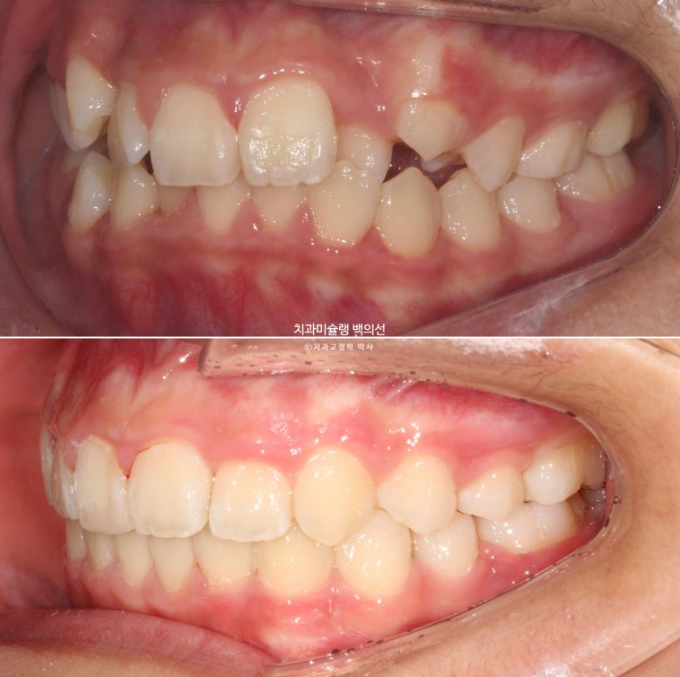

24년 1월 교정치료를 위해 온 만 10세 어린이 입니다.

3년 전에 소아치과에서 앞니 부분교정을 한 적이 있다고 합니다.

그래서 위 앞니에는 중절치 두 개를 잇는 철사유지장치가 붙어있었습니다.

중심선이 약 2mm 어긋나 있으며 위 앞니 치축은 한쪽으로 기울어져 있습니다.

앞니가 깊게 물리는 과개교합도 보입니다.

악궁확장을 통한 덧니배열을 목표로 인비절라인퍼스트 교정치료 권유드렸습니다.